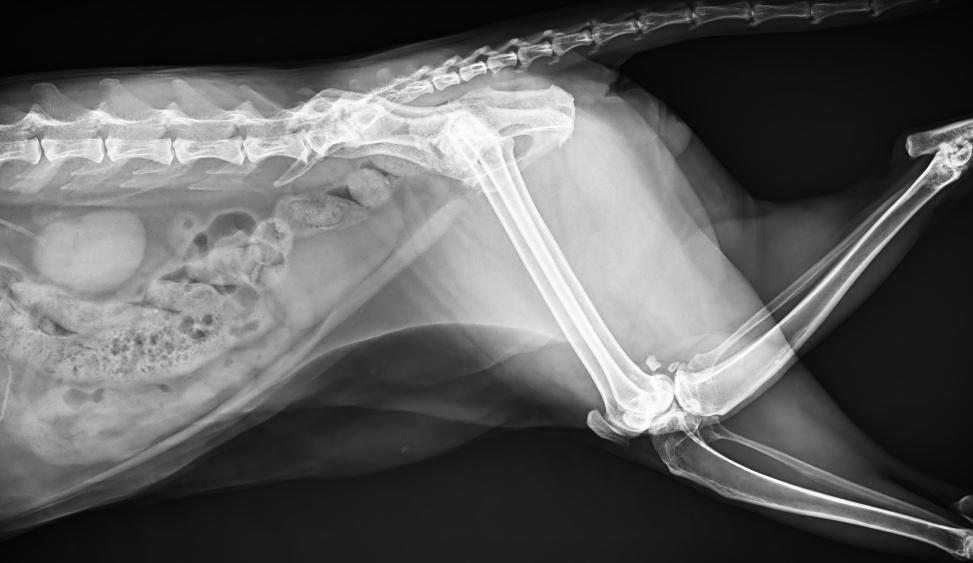

● 17*17大尺寸平板探測(cè)器,獲得高質(zhì)量圖像

● 優(yōu)異的空間分辨率及信噪比,提升圖像質(zhì)量

● 進(jìn)口高品質(zhì)球管,大功率、高熱容量、微焦點(diǎn),1.0/2.0mm雙焦點(diǎn)設(shè)計(jì)

● 25kHz高主逆變頻率,輸出電壓更穩(wěn)定;瞬時(shí)定格影像,無(wú)拖尾現(xiàn)象

● 智能高效的圖像處理軟件,大幅提升圖像質(zhì)量